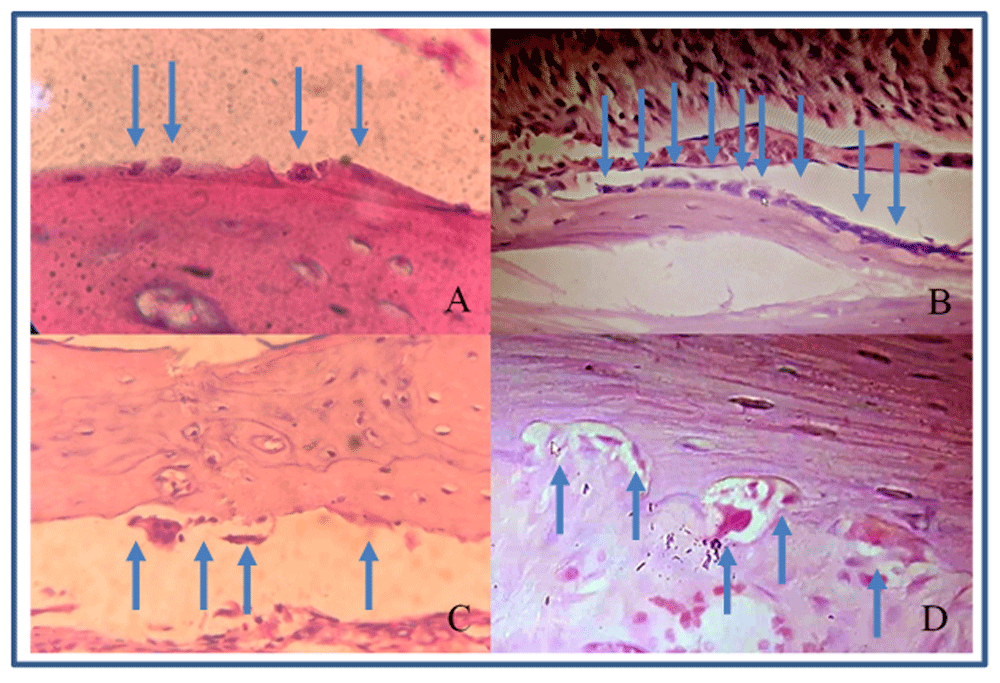

The number of osteoblasts in group 2 were higher compared with group 1 at each time point (Figure 2A and B; Table 2). These differences were statistically significant (p<0.05). Group 2 showed increased osteoblasts starting from day 0 to day 3, while group 1 had decreased osteoblast after day 3.

(A) osteoblasts in group 1 (control); (B) osteoblasts in group 2 (vitamin E treatment); (C) osteoclasts in group 1; (D) osteoclasts in a Howship’s lacuna in group 2.

The number of osteoclasts in group 2 were higher than group 1 except on day 1, but the differences were not significant statistically (Figure 2C and D; Table 3).

Our results showed that the number of osteoclasts is higher in group 2 compared to group 1 although the difference was not statistically significant. Miresmaeili et al., in their study on the effect of vitamin C to orthodontic tooth movement, found that osteoclast numbers were significantly higher in the vitamin C group, which hence accelerates tooth movement22. Kale et al., in their research on vitamin D injection, observed a significant amount of Howhip’s lacunae in resorption cavity as a result of osteoclast’s activity23. Future research is required to observe the comparison between Howship’s lacunae and osteoclasts numbers.

In our study, there were statistically significant differences in the mean number of osteoblast cells between both groups at each time observed. Kawakami and Takano-Yamamoto demonstrated an increased osteoclast and osteoblast number with local injection of 1,25-dihydroxyvitamin D3 in the submucosal palatal area of rats subjected to tooth movement on day 7. Increased osteoblast counts were observed on day 1419,24. In another study, Feresin et al. reported that the formation rate and bone volume increased significantly by 65% in rat bone, who were given a vitamin E diet compared to the control group. Their result indicated that a vitamin E diet was able to increase the process of mineralization and bone formation mediated by osteoblast cells25. Diravidamani et al. stated that many drugs that are used to reduce pain had effects on orthodontic tooth movement. Further research should be done to observe vitamin E on pain regulation, because it has anti-inflammatory effect, which is assumed to reduce pain in orthodontic treatment10,26–28.